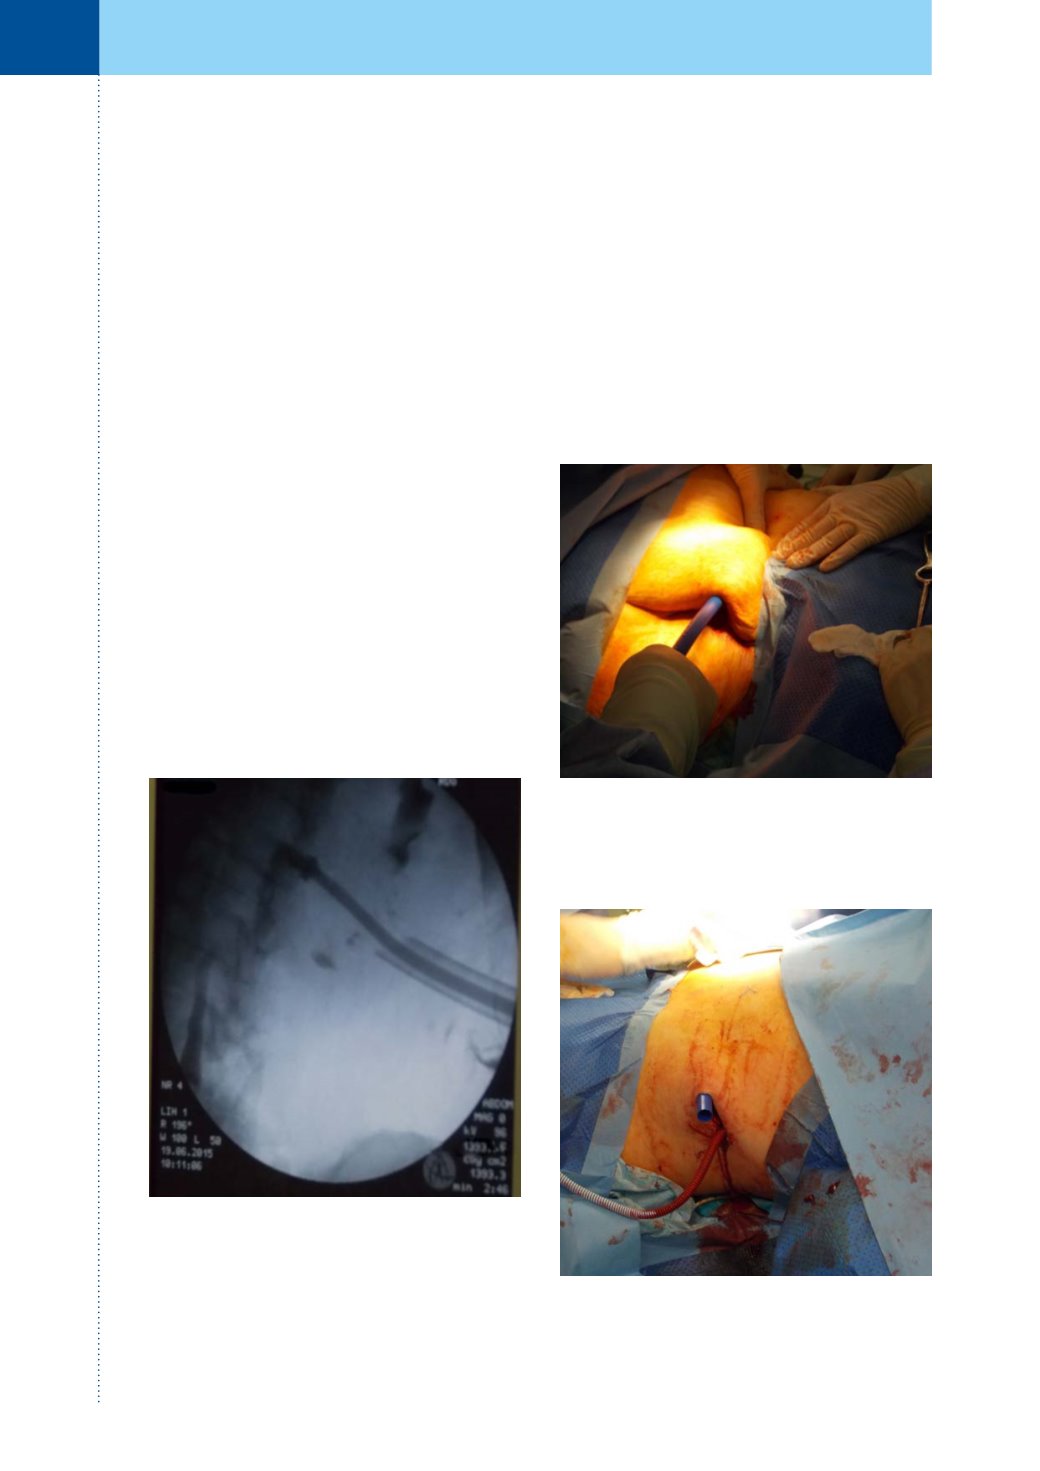

Zákrok byl proveden v celkové anestezii. Při za-

vádění byla využita již existující nefrostomie vle-

vo. Do ní jsme zavedli vodič, poté jsme vytáhli

nefrostomický drén a po zavedeném vodiči jsme

provedli dilataci kanálu na 30F. Pod rentgenovou

kontrolou jsme zavedli proximální konec extra-ana-

tomického stentu do ledvinové pánvičky. Správné

uložení proximálního konce stentu bylo možno

kontrolovat skiaskopicky, jelikož zakončení Detour©

extra-anatomického stentu je opatřeno speciálním

rentgen–kontrastním prstencem (obrázek 1).

Obr. 1.

Skiaskopická kontrola správného uložení

rentgen kontrastního prstence proximálního konce

stentu v ledvině

Obr. 3.

Příprava stentu k zavedení do tunelizátoru

Fig. 3.

Preparation of the stent to insertion into the

plastic hollow tube

Obr. 2.

Tunelizování podkoží speciálním tunelizá-

torem

Fig. 2.

The plastic hollow tube is used to create a sub-

cutaneus tunnel

V místě původního vpichu nefrostomie pro-

vedena kožní incize, další kožní incize provedena

v blízkosti vyústění ureteroileostomie (obrázek 5).

Přiloženým tunelizátorem byl vytvořen prostor

v podkoží pro střední goretexovou část stentu (ob-

rázky 2 a 3). Středem tunelizátoru protažen De-

tour© extra-anatomický stent (obrázek 4). Délka

stentu byla upravena odstraněním jeho přeby-

tečné vnější goretexové části a zkrácením vnitřní

silikonové hadice, která byla protažená incizí do